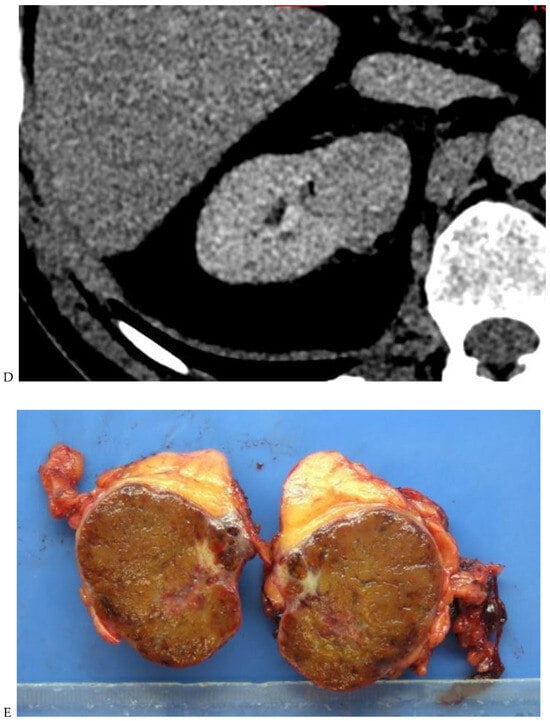

Figure 3.

CT aspect of a chromophobe renal cell carcinoma in the left kidney of a 68-year-old-woman. (A) Unenhanced image. Presence of an isodense, homogeneous solid lesion at the medium part of the left kidney. (B) It appears moderately hypervascularized on the corticomedullary phase image, with hyperdense septa. (C) There is progressive washout on the nephrographic phase image and the lesions appears hypodense relative to the renal parenchyma (C). (D) Macroscopic view of the lesion after partial nephrectomy. Courtesy of Pr S. Ferlicot, Department of Pathology, Bicêtre Hospital.